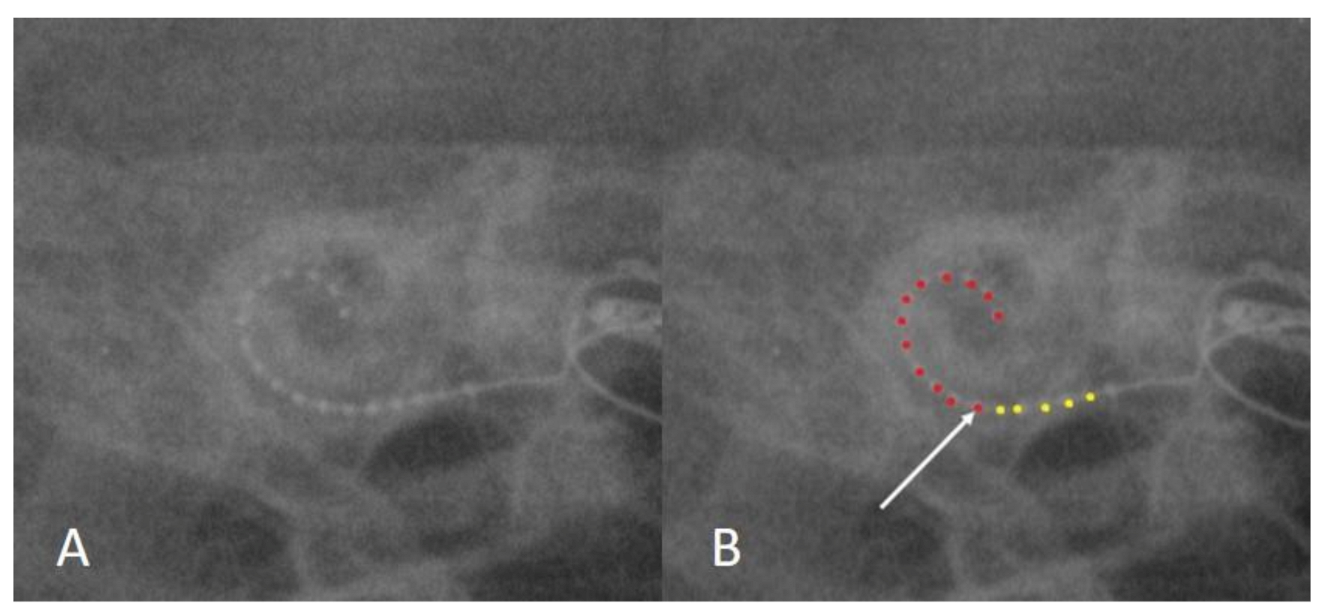

3.2. Case 2: Incomplete Insertion